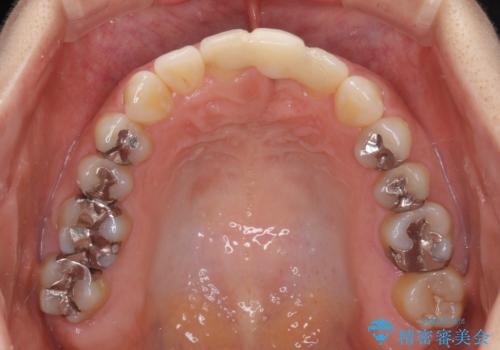

- 接着タイプの前歯のブリッジが不自然であるとのことで来院された患者様です。

欠損部の歯肉が窪んでいるため、歯肉移植により形態を改善し、オールセラミックブリッジにて補綴することとしました。

事前に装着されていた接着タイプのブリッジは、歯の切削量が少ない反面、接着界面から虫歯が進行しやすく、脱落リスクが高くなるというデメリットがあります。